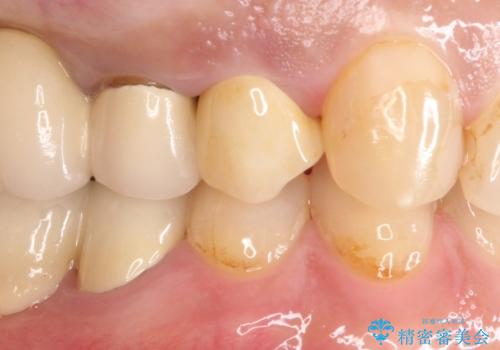

拡大鏡にて虫歯を除去。精度の高いセラミッククラウン

- 以前治療したセラミックインレーが破折したことを主訴に来院されました。

咬合力が強く、残存歯質が少ないためオールセラミッククラウンによる治療を行いました。

今回は白い材料での修復を希望されたため、欠けるリスクが高いセラミックインレーは避け、セラミッククラウンにて治療を行いました。